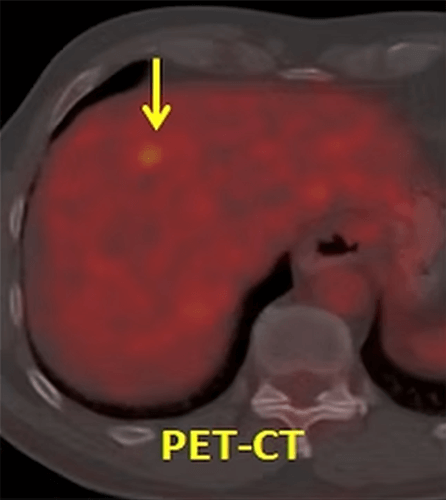

Our patient had rectal cancer (*) on PET-CT and underwent 3 sessions of intraarterial chemotherapy via the feeding artery. The control PET-CT showed that the tumor (*) has almost disappeared. The patient was operated and the specimen showed no viable tumor cells in the rectum (complete pathologic response).